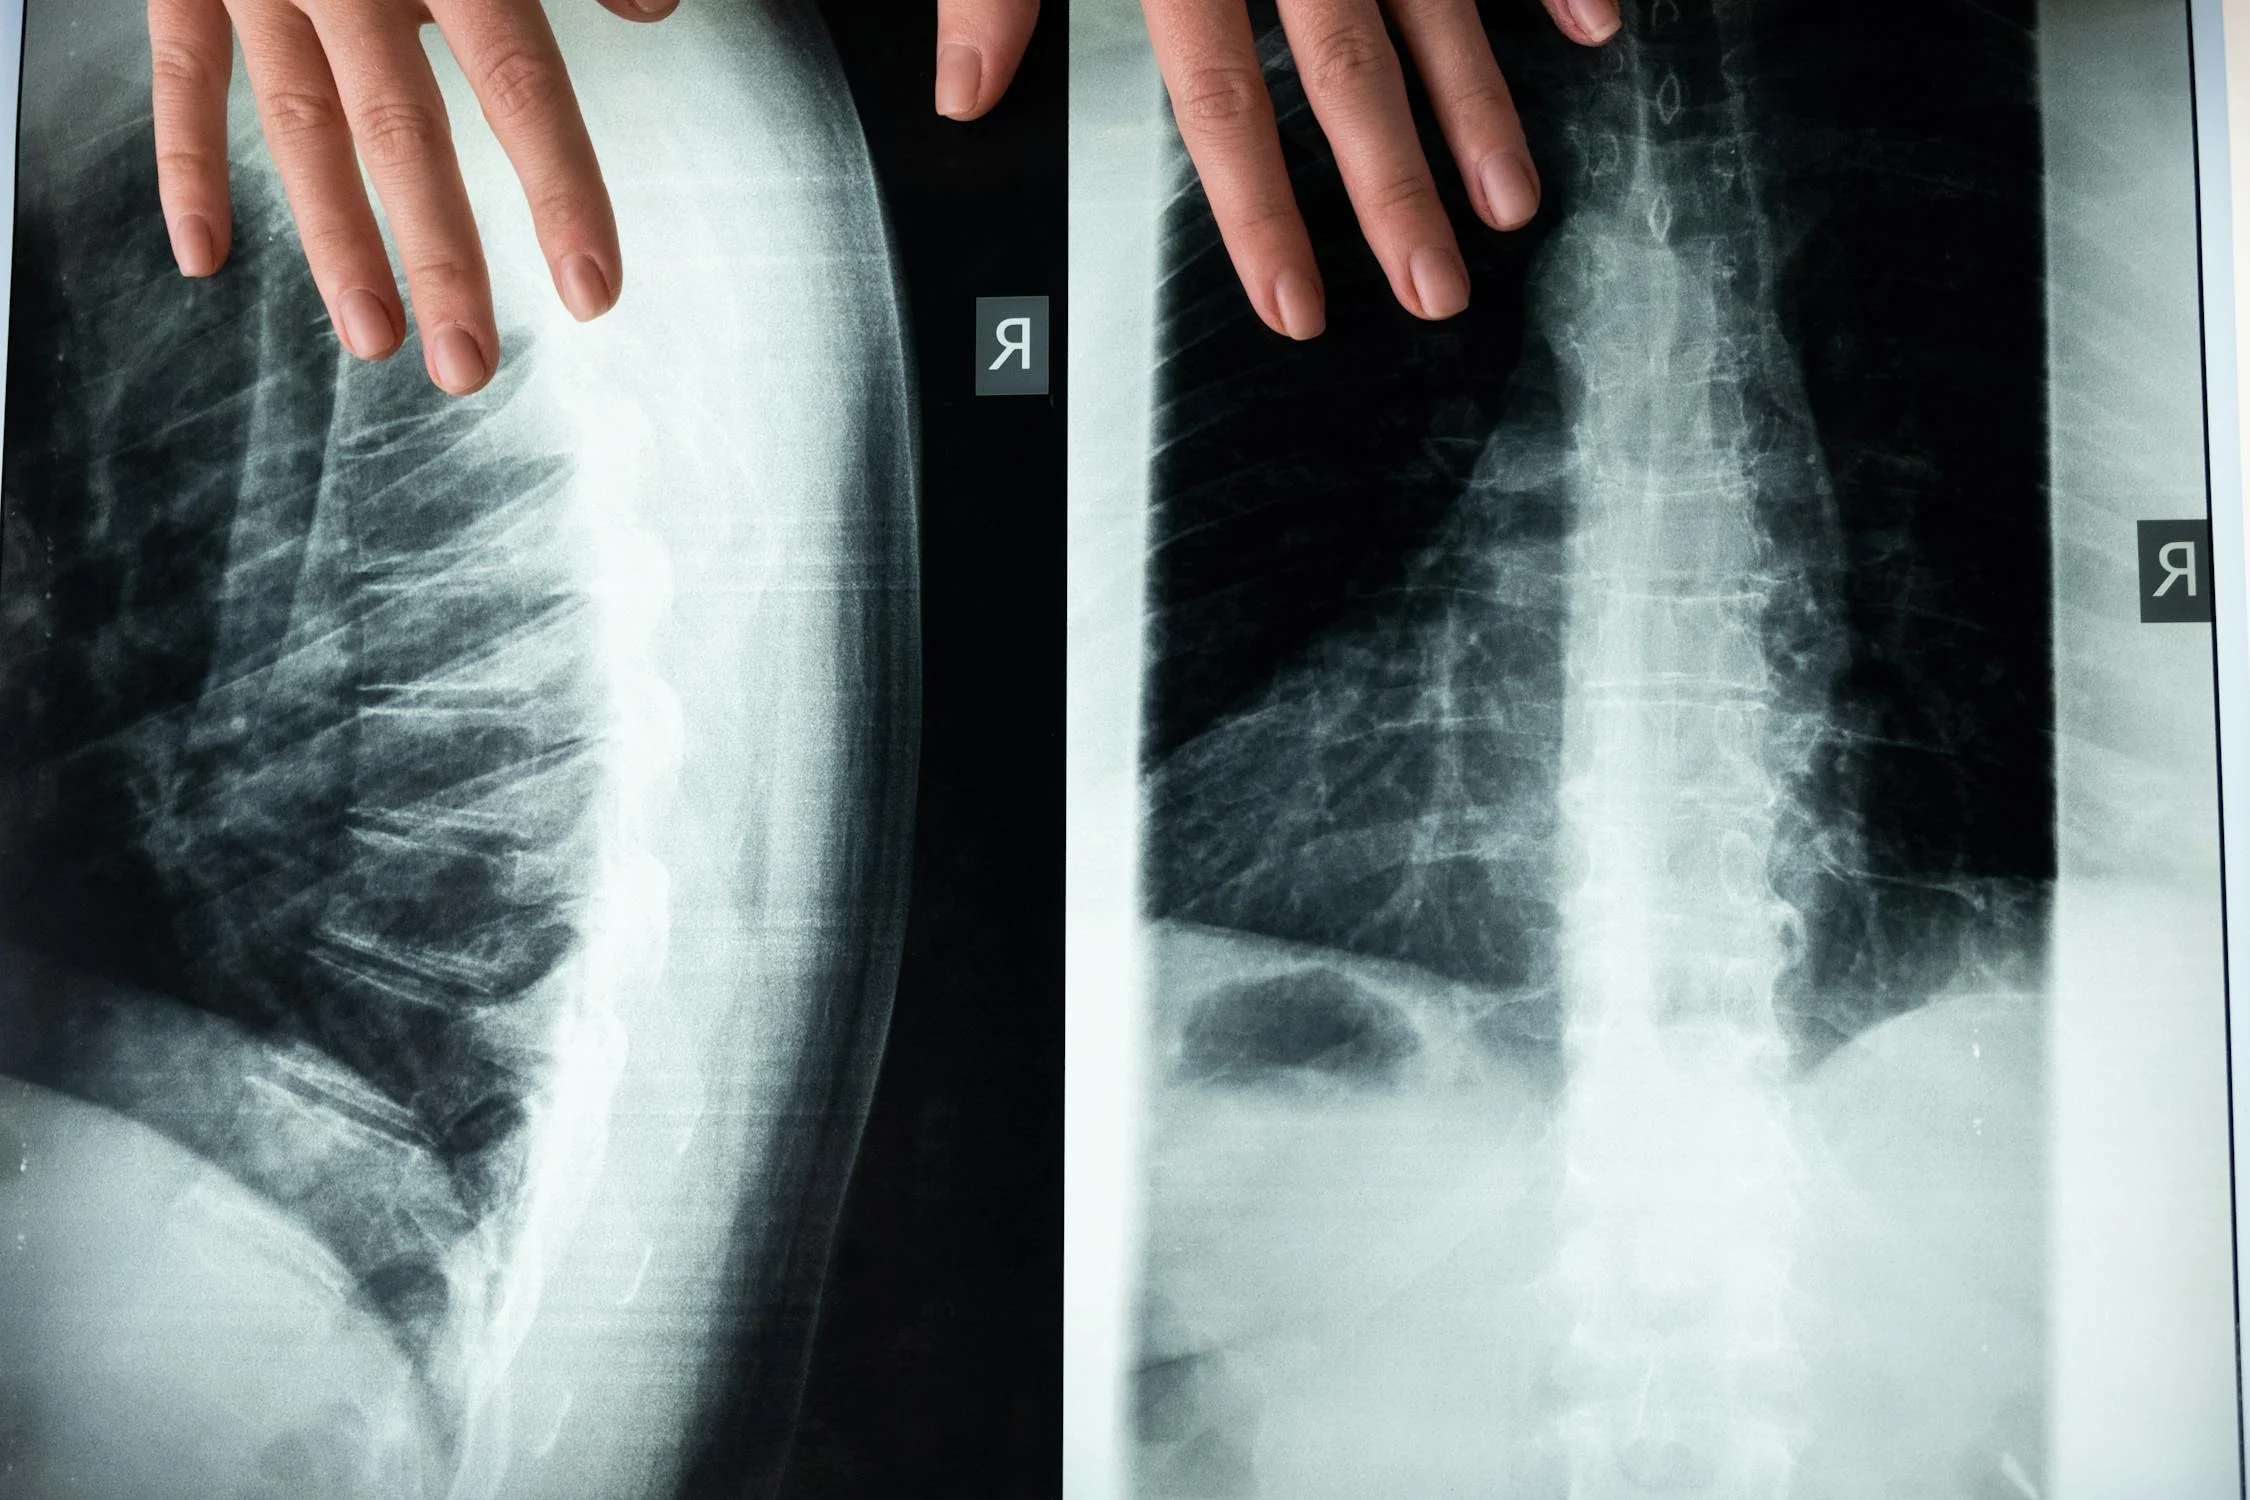

Medical imaging helps doctors figure out what's going on inside your body by taking pictures of your insides. This is important for diagnosing things like broken bones, finding out what's causing abdominal pain, or seeing how bad injuries are after an accident. Giving doctors the right medicine quickly helps prevent problems and makes recovery more likely for patients.

Imaging tests can help doctors in emergencies to quickly figure out what's wrong with a patient. X-rays, CT scans, and ultrasounds are some of the tests they might use to check for injuries from accidents or trauma. If they diagnose the problem quickly, they can give the patient the right treatment, which can prevent bigger problems and even save lives.